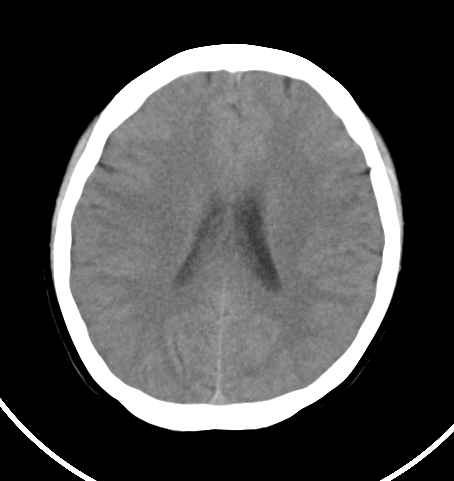

病人女 35岁 自述头晕 头痛

双侧基底节区及右侧丘脑区多发点状钙化,周围未见水肿及占位征象.余未见明显异常.考虑:脑囊虫病<囊虫的退变或死亡期>请结合有无相关病史.

以下是引用苯小孩在2007-4-20 15:47:00的发言:[br]双侧基底节区及右侧丘脑区多发点状钙化,周围未见水肿及占位征象.余未见明显异常.考虑:脑囊虫病<囊虫的退变或死亡期>请结合有无相关病史.

颅内有散在钙化

脑囊虫病理性钙化。